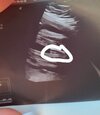

Cześć dziewczyny, powiedzcie czy jest tutaj cień szansy na dziewczynkę? W 12+1 z wyrostka była dziewczynka, w 16 tyg też raczej dziewczynka, a na ostatniej wizycie w 20+1 tyg dostałam takie zdjęcia 🙄 czy to może być rączka między nogami lub pępowina? Na tym zdjęciu nie do końca chyba jak chłopiec 😏

Cześć dziewczyny. Od początku ciąży zarówno lekarz z prenatalnych jak i mój lekarz mowią ze bedzie dziewczynka. Na 2 prenatalnych lekarz powiedział ze dziecko zle ułożone ale wydaje mu się ze chlopczyk. Teraz 26 tydzień. Moja lekarka mowi bez wątpliwości, że widzi wargi sromowe. Za 2 tyg mam 3 prenatalne ale ciekawość mnie zżera. Co myślicie o tym? Czy to faktycznie mogą być wargi? :) położna twierdzi ze na zdjęciu z prenatalnych to bardziej pepowina niż siusiak